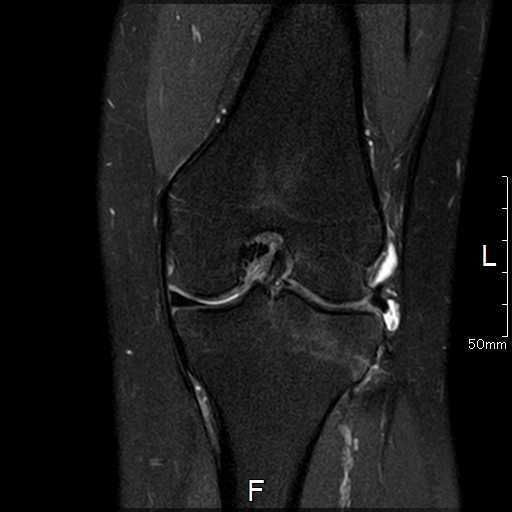

MRI所見

| 手術前 | 手術後 |

![]() ![]() | ![]() ![]() |

| 関節水腫、骨髄浮腫を認める | 術前認めた水腫などの所見はなし |